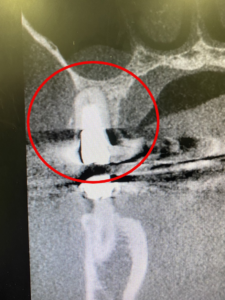

こちらはCTレントゲンの写真です。

その後、左上の一番奥の歯も同様の流れでインプラント治療を行いました。